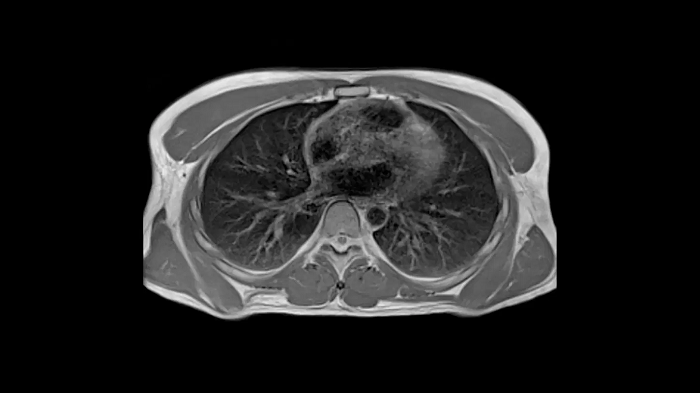

New opportunities in pulmonary imaging with High-V MRI

Pulmonary imaging has been disreputably challenging with traditional MRI as the air-tissue interfaces lead to fast signal decay. These challenges scale with magnetic field strength which makes High-V MRI the perfect opportunity for pulmonary imaging. Consequently, High-V MRI has the ability to extend the reach of pulmonary MRI.

80 cm bore MAGNETOM Free.Max

Image Courtesy: University Hospital Erlangen, Germany | Image-ID: 4aaaa0419